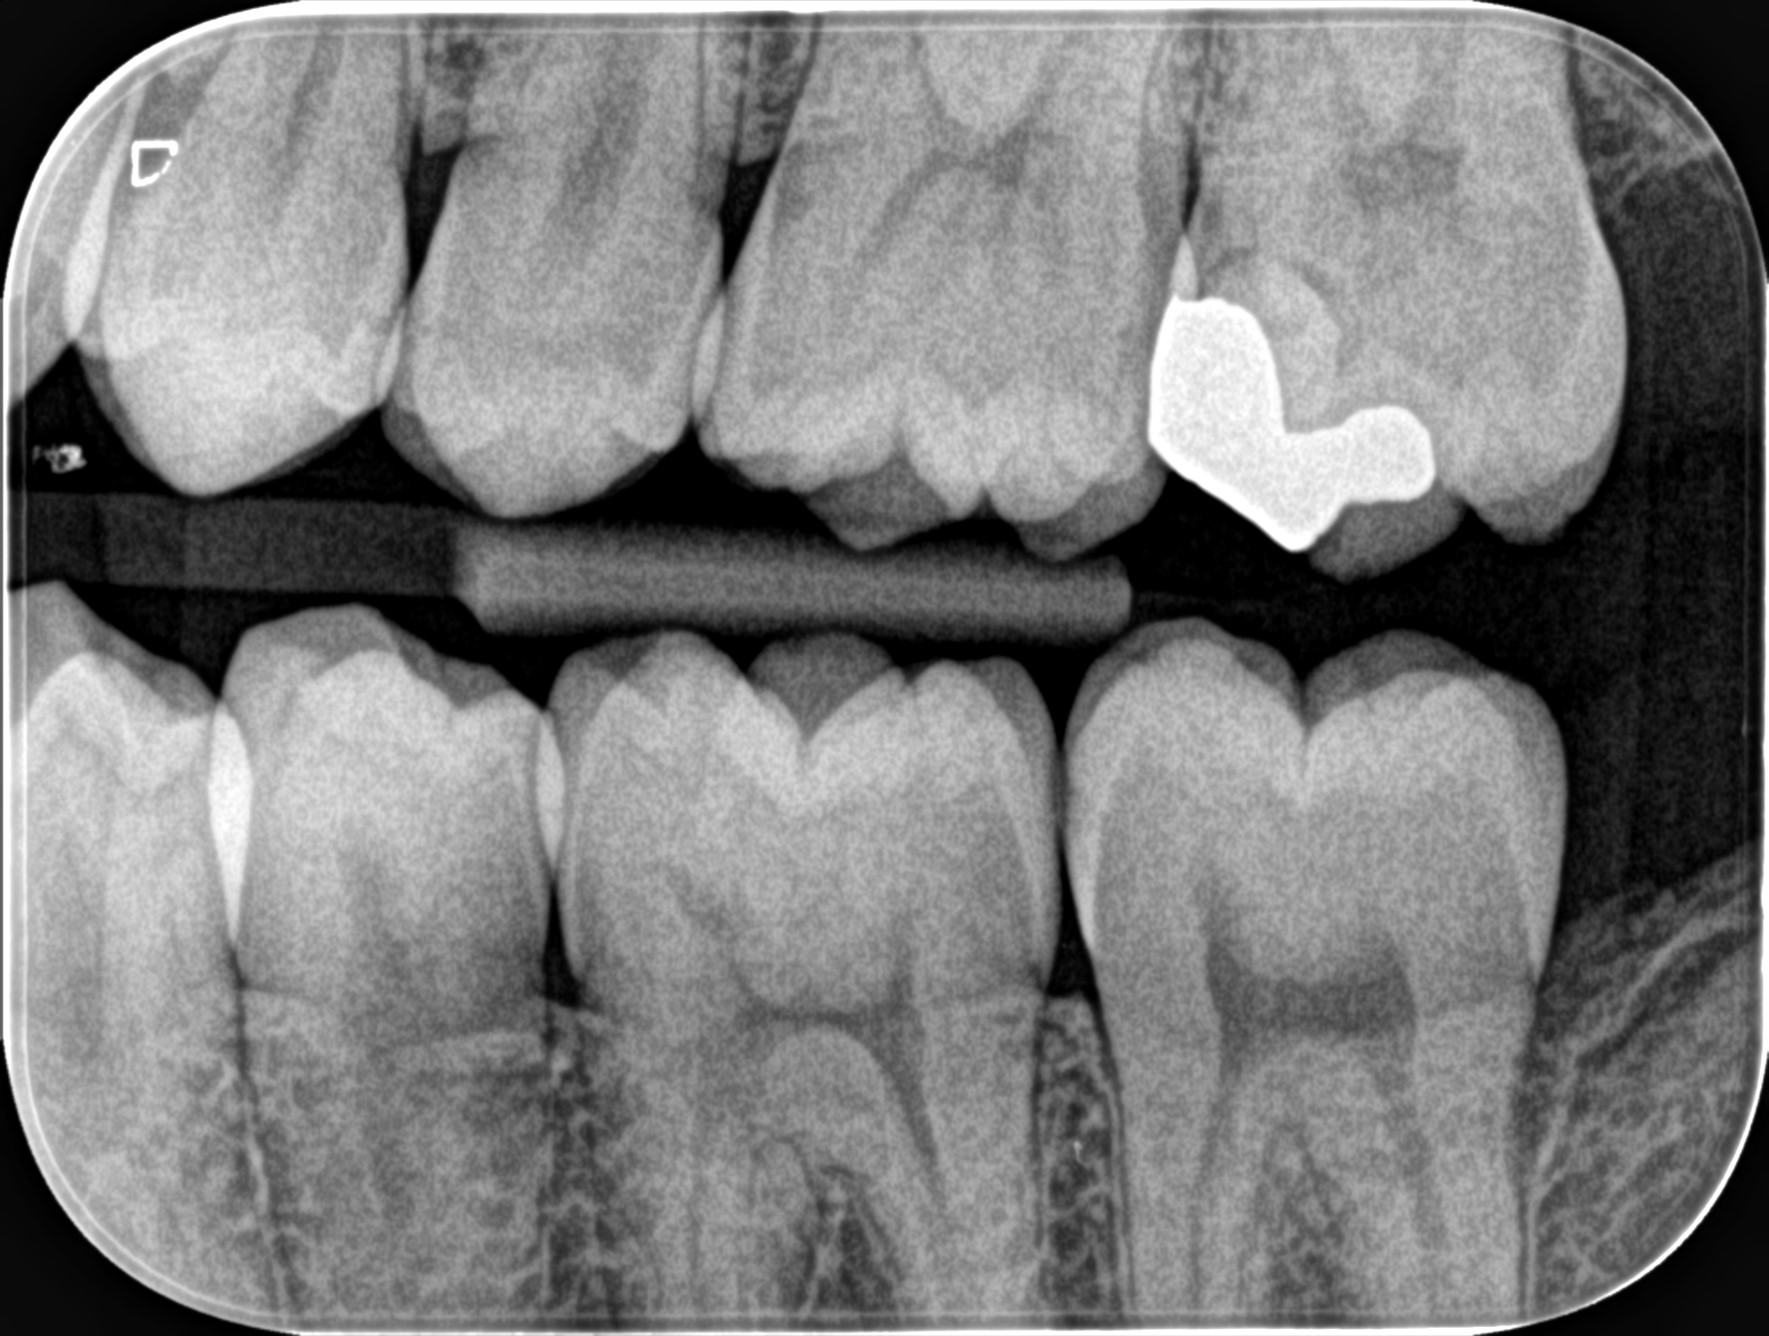

現代の歯科矯正技術は飛躍的に進歩しており、目立たない矯正装置や短期間で効果を得られる治療法が増えています。これにより、大人でも安心して治療を受けることができる環境が整っています。